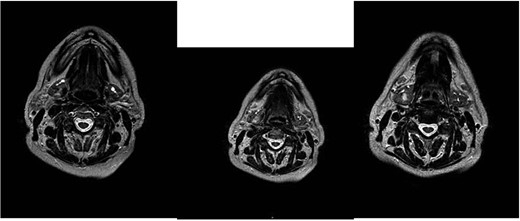

This hypothesis was questioned by magnetic resonance imaging (MRI), which highlighted the presence of an ovoid expansive process of ⁓15 mm in diameter with undefined margins compared to the surrounding glandular parenchyma. The MRI characteristics suggested an aggressive lesion such as adenocarcinoma: the lesion was characterized as an area with a non-homogeneous signal for T2 iso-hyperintensity and T1 iso-hypointensity with equally heterogeneous enhancement after administration of the contrast medium (Fig. 1).

MRI with the contrast medium which highlighted the presence of an ovoid expansive process of ⁓15 mm in diameter with undefined margins compared to the surrounding glandular parenchyma. The lesion was characterized as an area with a non-homogeneous signal for T2 iso-hyperintensity and T1 iso-hypointensity with equally heterogeneous enhancement after administration of the contrast medium.